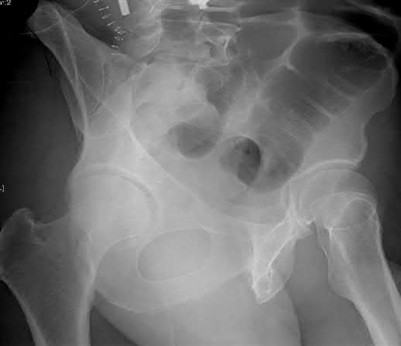

Question 4:

A 12-year-old obese male presents with a stable slipped capital femoral epiphysis (SCFE) of the left hip. Which of the following factors is the strongest indication for prophylactic in situ pinning of the asymptomatic contralateral right hip?

Correct Answer: Presence of an underlying endocrine disorder (e.g., hypothyroidism)

Prophylactic pinning of the contralateral hip in SCFE is controversial but is strongly indicated in patients with a high risk of bilateral involvement. Risk factors predicting contralateral slip include an underlying endocrine disorder (such as hypothyroidism, panhypopituitarism, or renal osteodystrophy), prior radiation therapy, or age of presentation less than 10 years (or low modified Oxford bone age score).